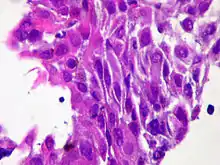

Micrograph of squamous-cell carcinoma (H&E stain)

Squamous epithelial cells are not found in normal thyroid, thus the origin of SCT is not clear. However, it might be a derived from the embryonic remnants such as thyroglossal duct or branchial clefts. Often SCT is diagnosed in one of the thyroid lobes, but not in the pyramidal lobe. Another possible way of SCT development can be through the squamous metaplasia of cells. However, that theory is also controversial, since the Hashimoto's thyroiditis and chronic lymphocytic thyroiditis (neoplasms to be showed squamous metaplasia) are not associated with SCT. Primary STC is usually diagnosed in both lobes of thyroid gland. The histopathology of STC shows a squamous differentiation of tumor cells.